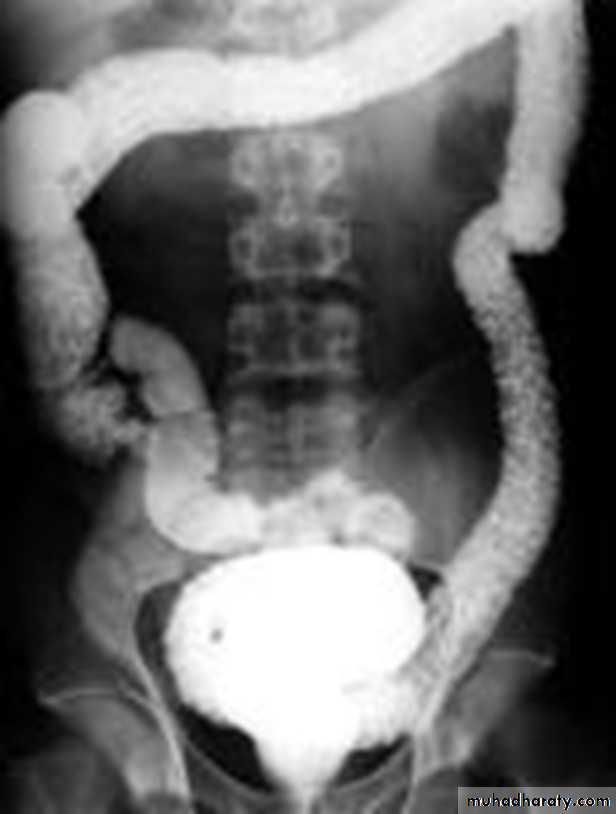

Barium enema

A: caecumB: ascending colon

C: transverse colon

D: descending colon

E: sigmoid colon

HF: hepatic flexure

SF: splenic flexure

F: terminal ileum